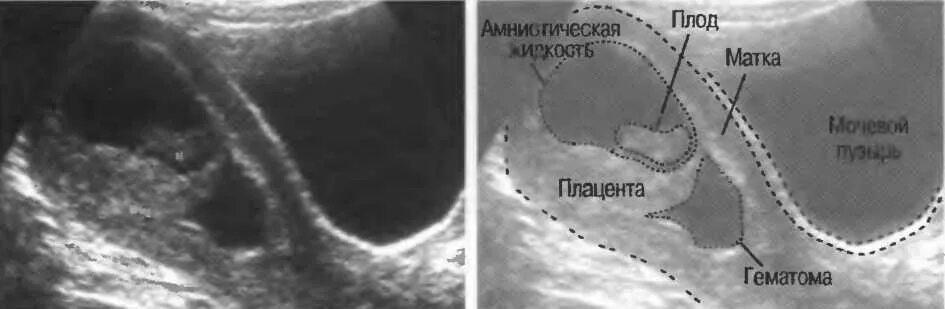

Как выходит гематома при беременности